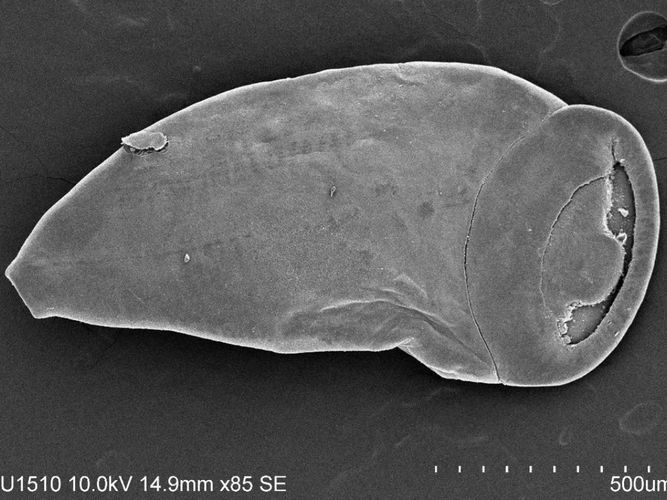

Our Parasite AI Imaging Project is designed to deliver rapid, scalable, and consistent parasite screening that strengthens both research and routine monitoring. Using standardized microscopy imaging paired with machine-learning models, we automate segmentation, counting, and preliminary classification so raw images become reliable, comparable metrics across samples, sites, and time. By flagging uncertain cases for expert confirmation, the project aims to speed turnaround, improve early detection and decision-making, and expand surveillance capacity without compromising biological oversight.